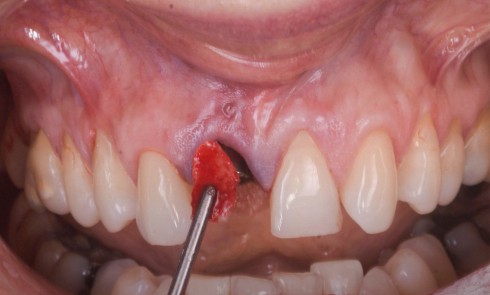

gestion des tissus mous péri-implantaires

Responsable de séance : Franck Afota Extraction–implantation immédiate (EII) : volumes osseux et gingivaux suffisants Lorsque les volumes osseux et gingivaux sont...